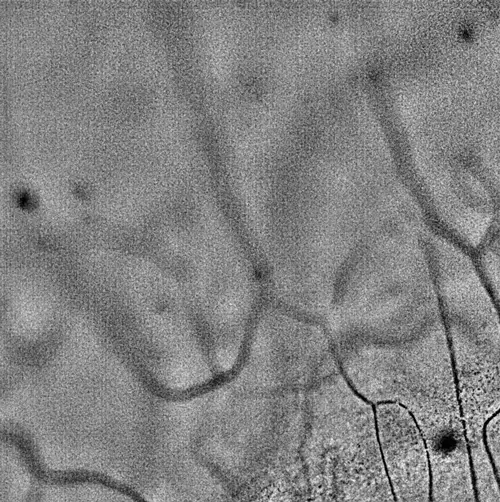

The world’s first imaging-based mucin layer diagnostic solution

We have developed the world’s first imaging technology for conjunctival goblet cells, a core innovation that enables the diagnosis of various ocular diseases, including dry eye disease. Goblet cells serve as definitive biomarkers for dry eye and play a crucial role in maintaining immune tolerance. This breakthrough technology holds potential for expansion into diagnostics for other

Goblet Cell Examination

Goblet cell examination, which was previously difficult to analyze

Non-invasive, high-precision analytical technology

Expansion of Moxifloxacin-Based Imaging Techniques

Improving Diagnostic Efficiency and Identifying Disease Associations through AI Technologies

We are enhancing diagnostic accuracy and efficiency by applying AI-based analysis to high-resolution ocular imaging data. By training machine learning models on micro-level features such as leukocyte movement, goblet cell density, and vascular patterns, we aim to uncover associations with various ocular diseases and broader systemic inflammatory or autoimmune conditions.

To support this, we are increasing investments in software and AI infrastructure, with plans to extend our AI diagnostic applications to areas such as systemic disease evaluation and drug response prediction in the near future.